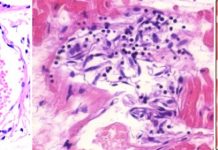

Vascular and organ damage induced by mRNA vaccines: irrefutable proof of causality

This article summarizes evidence from experimental studies and from autopsies of patients deceased after vaccination. The collective findings demonstrate that